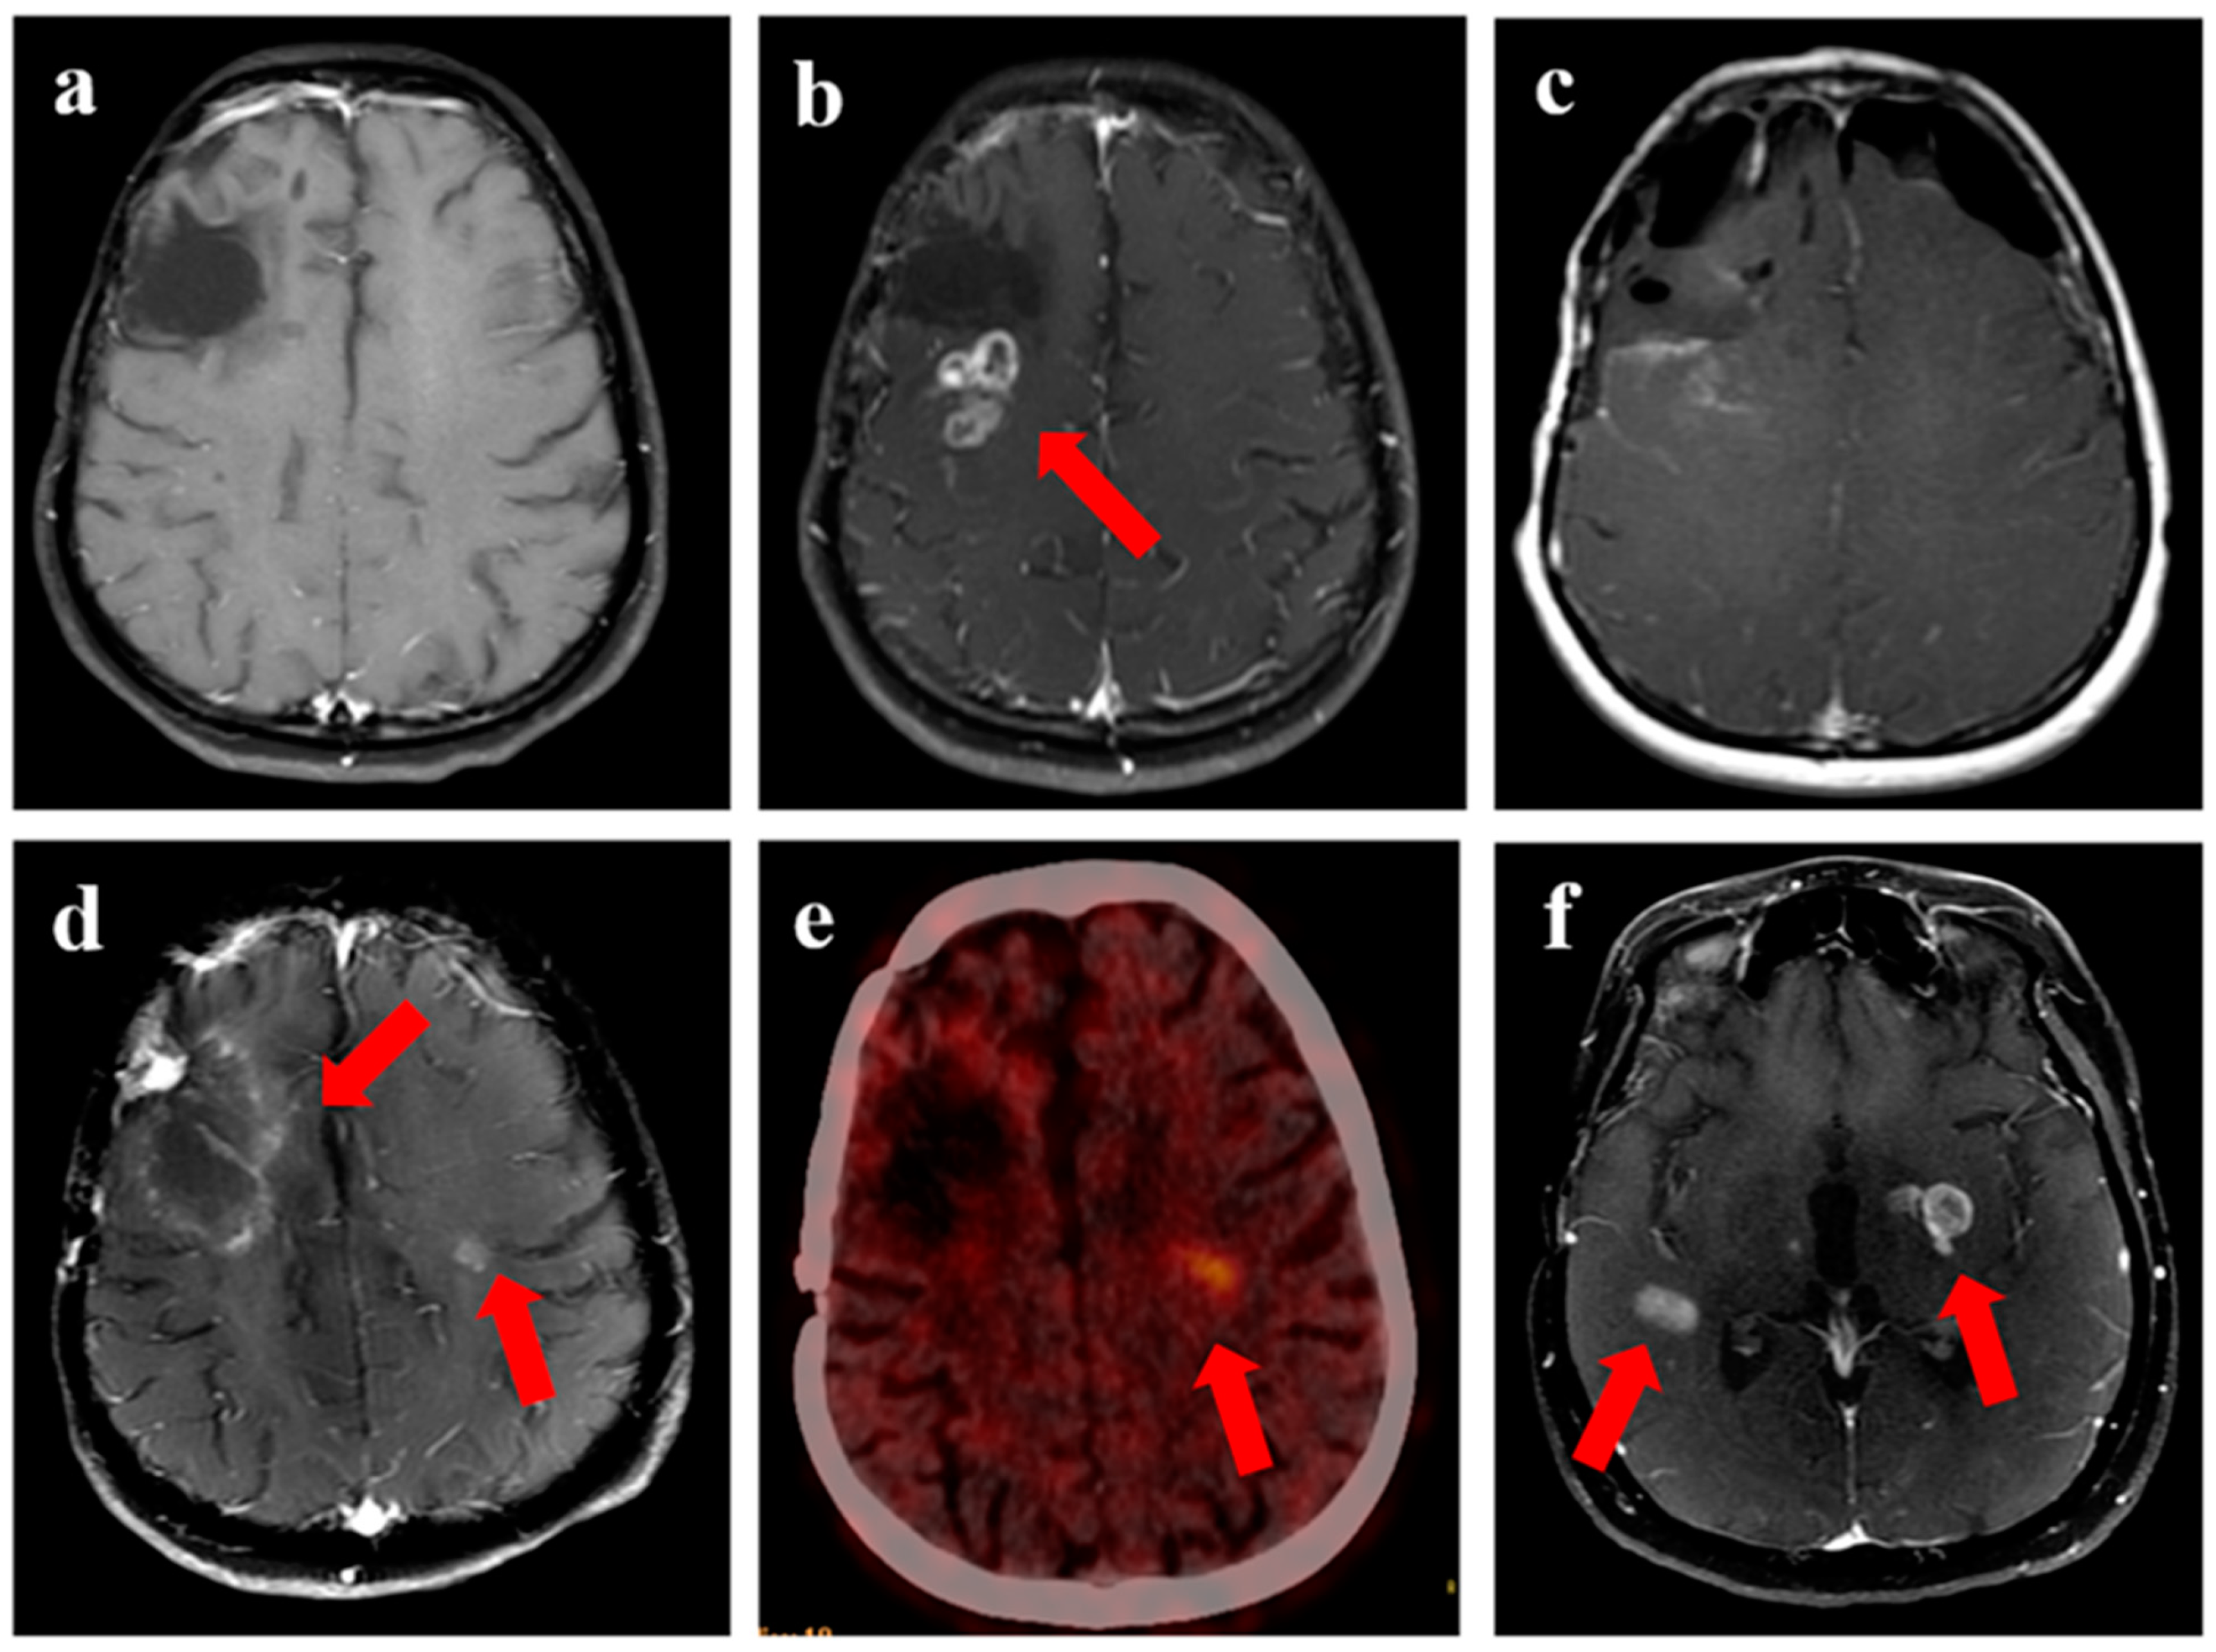

Figure 5.

Two patients with central recurrence, each in the upper and lower panel. (a) (37-year male with IDH-mutant astrocytoma) shows target volumes (GTV: red, CTV: blue; PTV: magenta) on T2-FLAIR MRI. The CTV was drawn to include all areas of T2w hyperintensity. (b,c) is T2-FLAIR and T1w contrast images showing recurrent disease (arrow) and its relation with the 95% isodose line (orange line). (d) (56-year male with recurrent glioblastoma) shows the target volumes for another patient volumes (GTV: red, CTV: blue; PTV: magenta) on T1w contrast MRI. The GTV was the enhancing disease, with CTV drawn as an expansion of 10 mm around the enhancing disease. (e,f) show the recurrence volumes with respect to target volumes and the 95% isodose line (orange), respectively. The major portion of recurrent disease can be seen lying within the 95% isodose line.